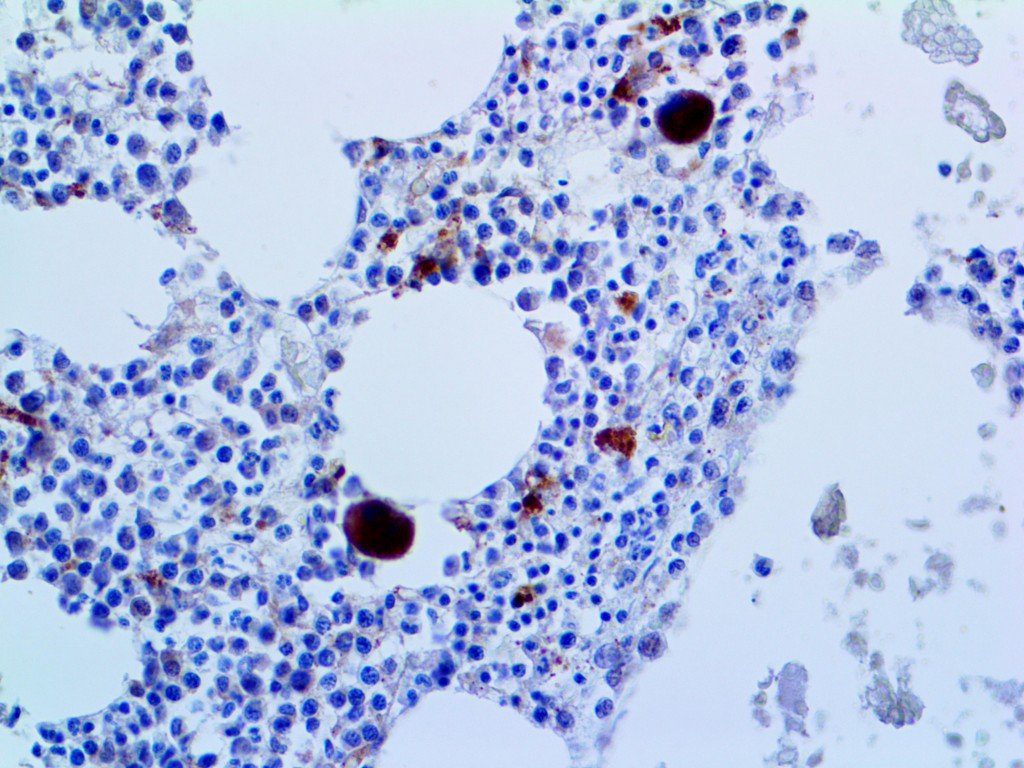

It is the ICU physician who is most likely to witness one of the deadliest manifestations of the abnormal immunological response, the cytokine storm syndrome (CSS). This response is also referred to by some as the cytokine release syndrome (CRS). CSS is characterized by continuous activation and expansion of macrophage and lymphocyte populations, which secrete large amounts of cytokines, causing the cytokine storm. This massive cytokine release is akin to hemophagocytic lymphohistiocytosis (HLH) disease, a syndrome characterized by initial unchecked and persistent activation of cytotoxic T lymphocytes and NK cells.

Clinical and laboratory manifestations of HLH include fever, enlarged liver and/or spleen, neurologic dysfunction, coagulopathy, liver dysfunction, cytopenias (i.e., low levels of erythrocytes, leukocytes, and/or platelets), hypertriglyceridemia, hyperferritinemia, hemophagocytosis, and eventually diminished NK cell activity as the immune system becomes progressively paralyzed. HLH can be familial (primary HLH) or secondary to another disease process (sHLH), such as rheumatic disease, in which it is referred to as macrophage activation syndrome (MAS, characterized by elevated ferritin).